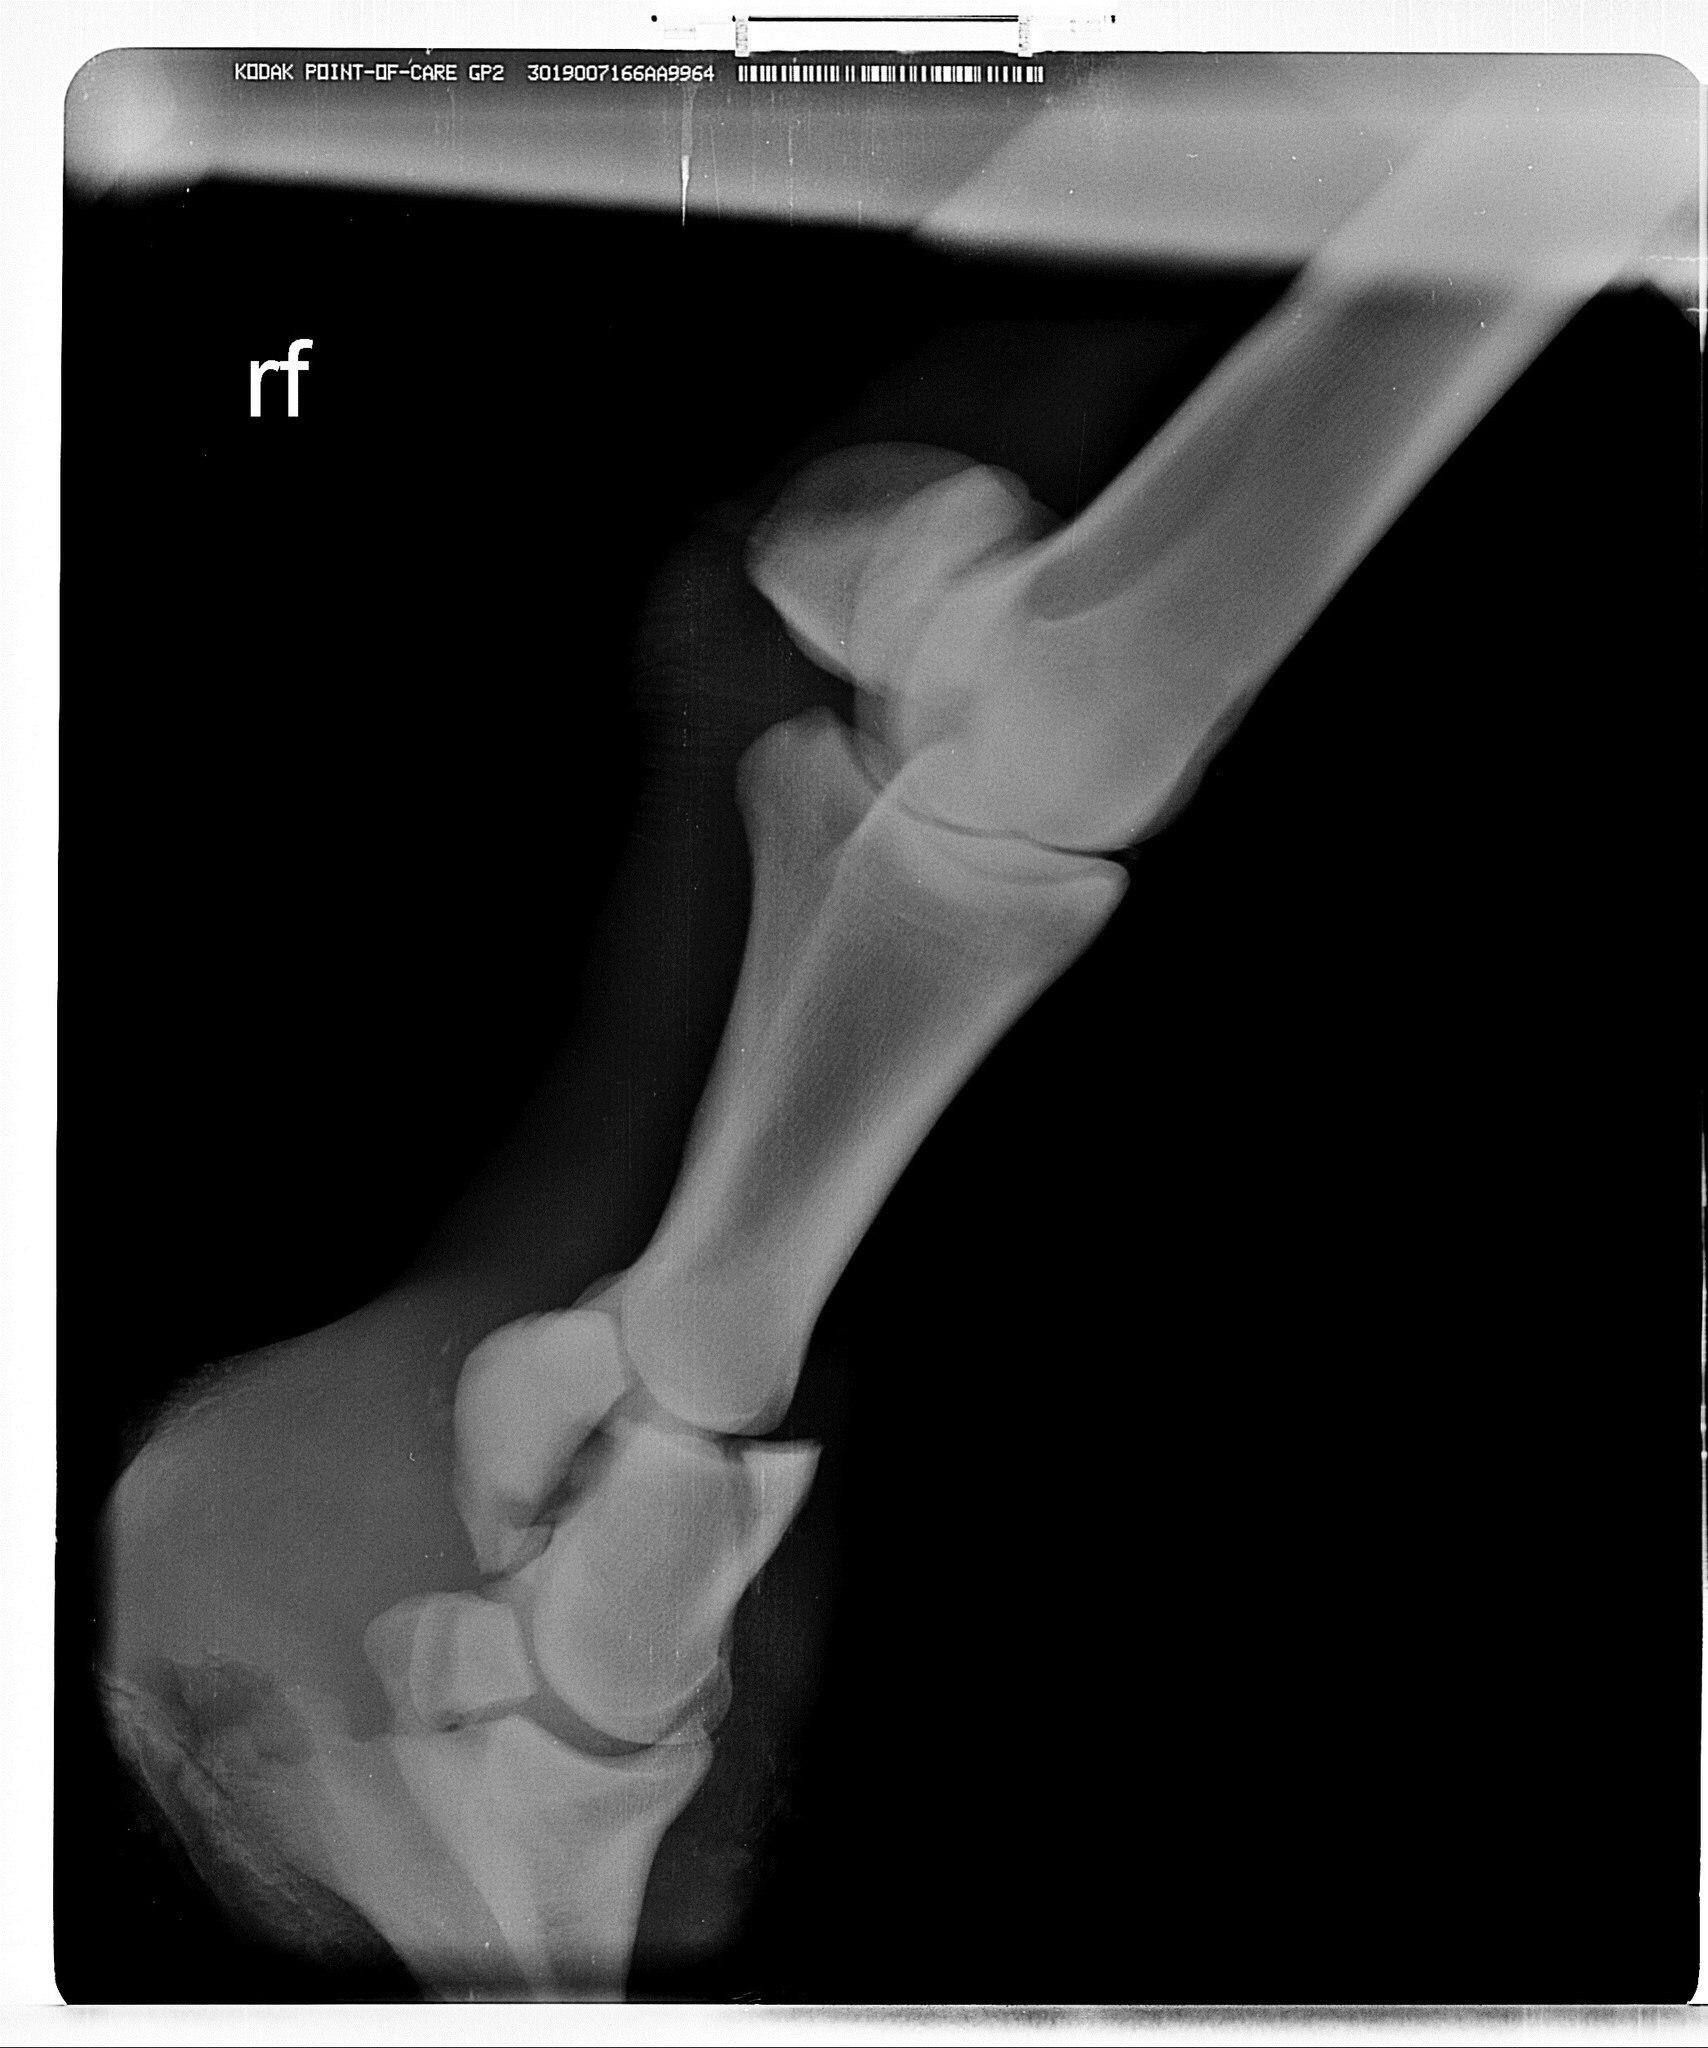

Жеребец. Винтовой перелом путовой кости на ЛЗ почти по всей её длине, внизу перелома смещение 5 отломков.

Брался НВ - остеосинтез на пластины и штифты. перегипсовка каждые определенные периоды. Наложение гипса при таких переломах отличается на передней ноге получен перелом или задней. На задней сложнее. Нужен наркоз каждый раз.

Стоял с гипсом 2,5 месяца, постоянные рентгены, жрал кучу всего. Гипс он как-то так продавил пяткой или что еще сделал, но получился, как костыль, на который он мог опираться и как-то даже перемещался по деннику. Сразу научился ложиться, вытягивая ногу и также вставать. Он сразу хотел жить и делал всё от него зависящее. Вот в этот период у него было отличное дыхание, что вообще никто не может объяснить.

Делающие рентгены ветеринары (Отрада, Эквимедика) говорили, что его случай противоречит медицинской практике и опыту. И что это магия